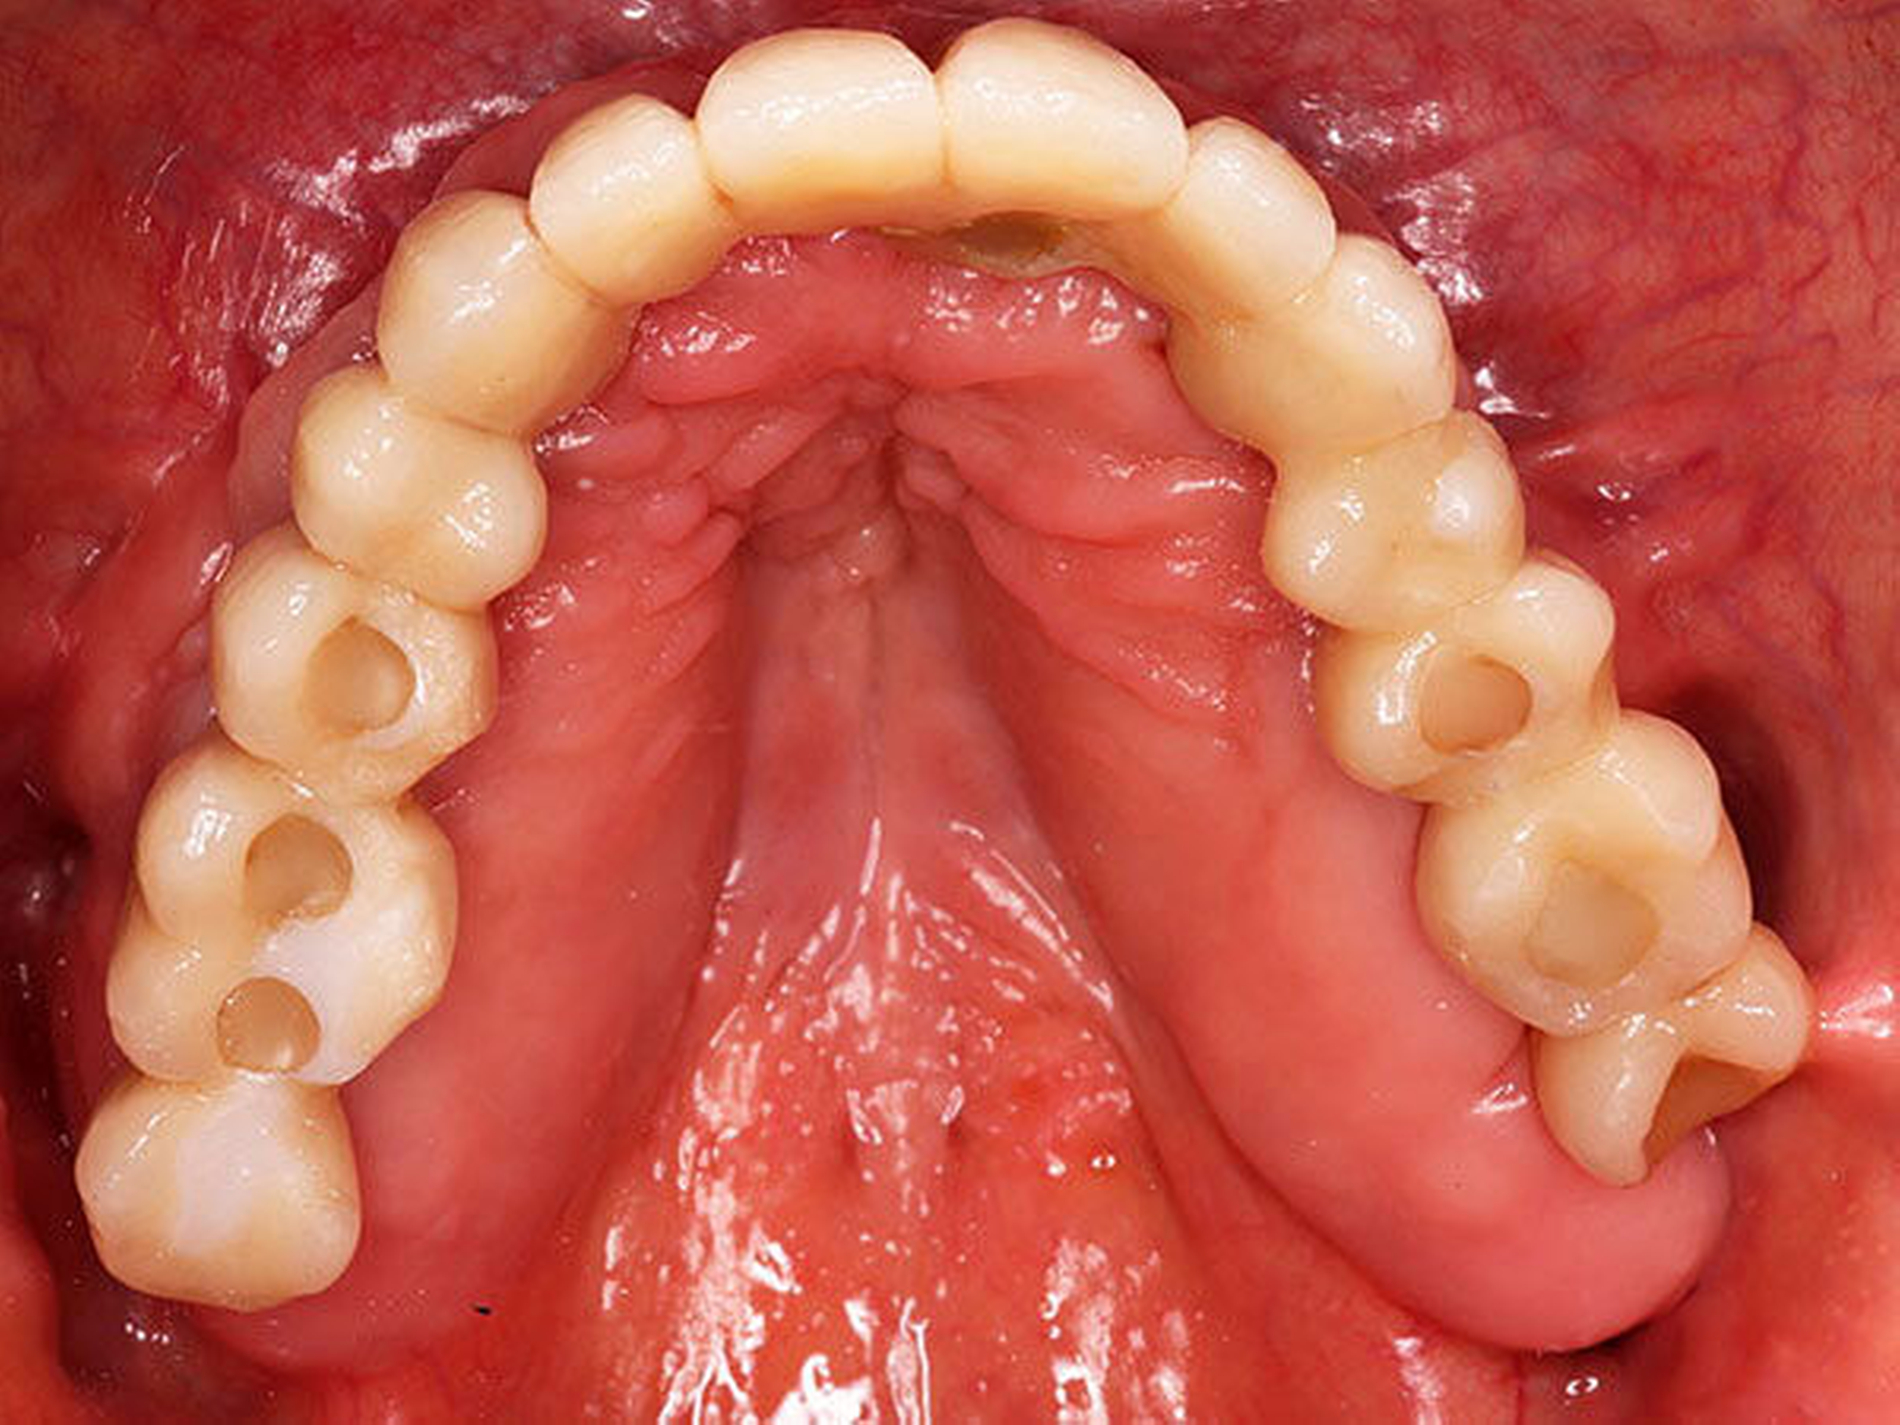

Die chirurgische Platzierung von Zahnimplantaten, das heißt die eigentliche Implantation, und die nachfolgende prothetische Versorgung dieser Implantate liegen nicht immer in einer Hand, sondern werden zum Teil von zwei verschiedenen Behandlern durchgeführt. Eine solche Arbeitsteilung hat durchaus Vorzüge: Aus der Allgemeinchirurgie wissen wir, dass Operateure mit großer Behandlungsroutine (hohe Fallzahlen pro Jahr) signifikant bessere Ergebnisse erzielen [Halm et al., 2002]. Doch geteilte Zuständigkeiten bergen auch Fallstricke: Wenn die Implantation und die nachfolgende prothetische Versorgung nicht gemeinsam geplant oder zumindest aufeinander abgestimmt werden, stellen sich im Fall eines ungünstigen Endresultats (Behandlungsfehler-Vorwurf) Fragen der Verantwortlichkeit. Man denke etwa an einen Fall, in dem ein Fachchirurg Implantate setzt, die aus Sicht des Implantatprothetikers falsch positioniert sind (Abbildungen 1, 2, 4, 5 und 6).

Letzterem bleibt nur die Wahl zwischen der Ablehnung der Weiterbehandlung und der Empfehlung einer aufwendigen und substanzverlustträchtigen Revision der Implantate (beides mutet dem betroffenen Patienten einiges zu) oder einer „Kompromissbehandlung“ mit dem Ziel, die invasive Revision der gesetzten Implantate abzuwenden und so den Schaden für den Patienten zu begrenzen. Heikel wird es insbesondere dann, wenn der Prothetiker in bester Absicht eine solche Kompromissbehandlung wagt, diese sich aber als nicht alltagstauglich erweist und der Patient schlussendlich Klage erhebt.

Hier kann es unter Umständen schwerfallen, die Verantwortung zuzuweisen: Liegt die Schuld beim Chirurgen, der die Implantate an ungünstiger Stelle gesetzt hat, oder beim Prothetiker, der sich nolens volens auf diese Situation eingelassen und ein letztlich unzureichendes Behandlungsergebnis erzielt hat? Aus fachlicher und ethischer Sicht ist die eigentliche Ursache für das insuffiziente Behandlungsergebnis beim Chirurgen zu suchen. Juristisch gesehen trägt dagegen jedoch der Implantatprothetiker die unmittelbare Verantwortung für das Behandlungsergebnis, da er die insuffiziente Suprakonstruktion geplant und eingegliedert hat. Rechtlich verhängnisvoll wird dieses Vorgehen insbesondere dann, wenn er den Patienten nicht explizit über den Kompromiss- und Versuchscharakter seiner Versorgung aufgeklärt hat oder das Aufklärungsgespräch und das Einverständnis des Patienten zur eigenen juristischen Absicherung nicht sorgsam dokumentiert hat.